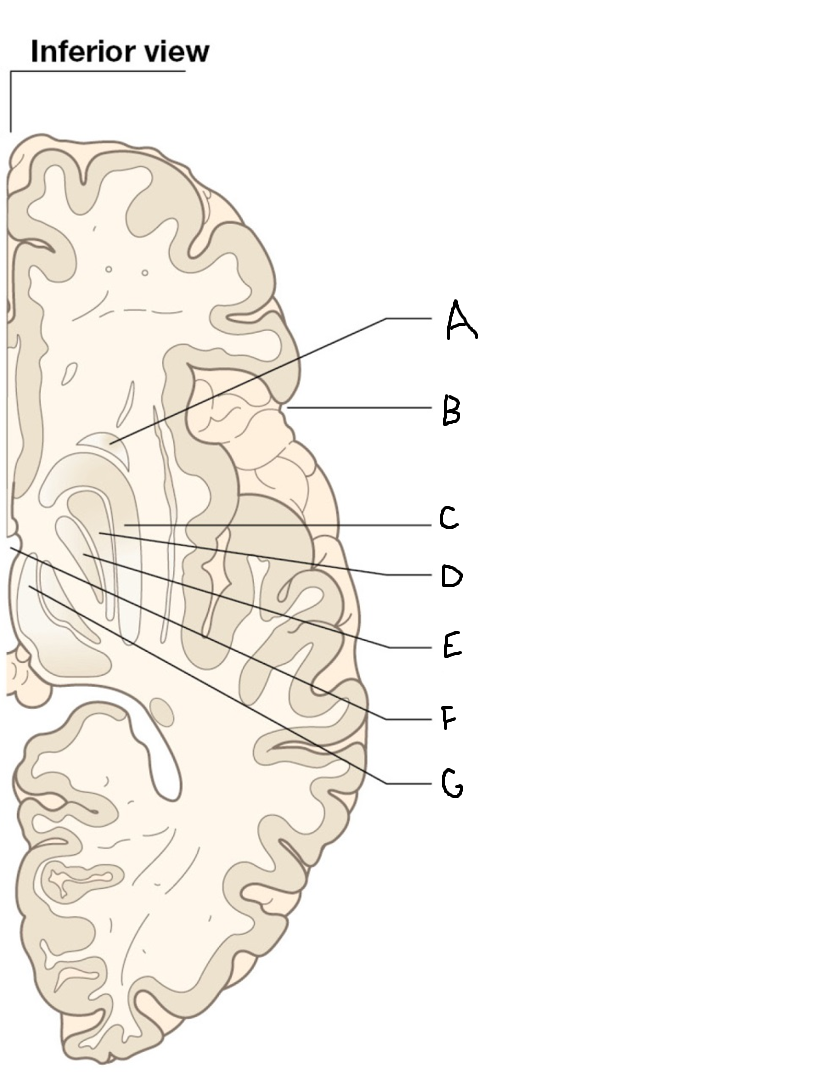

A

internal capsule (anterior limb)

B

caudate nucleus body

C

caudate nucleus head

D

putamen

E

caudate nucleus tail

F

thalamus

G

internal capsule (posterior limb)